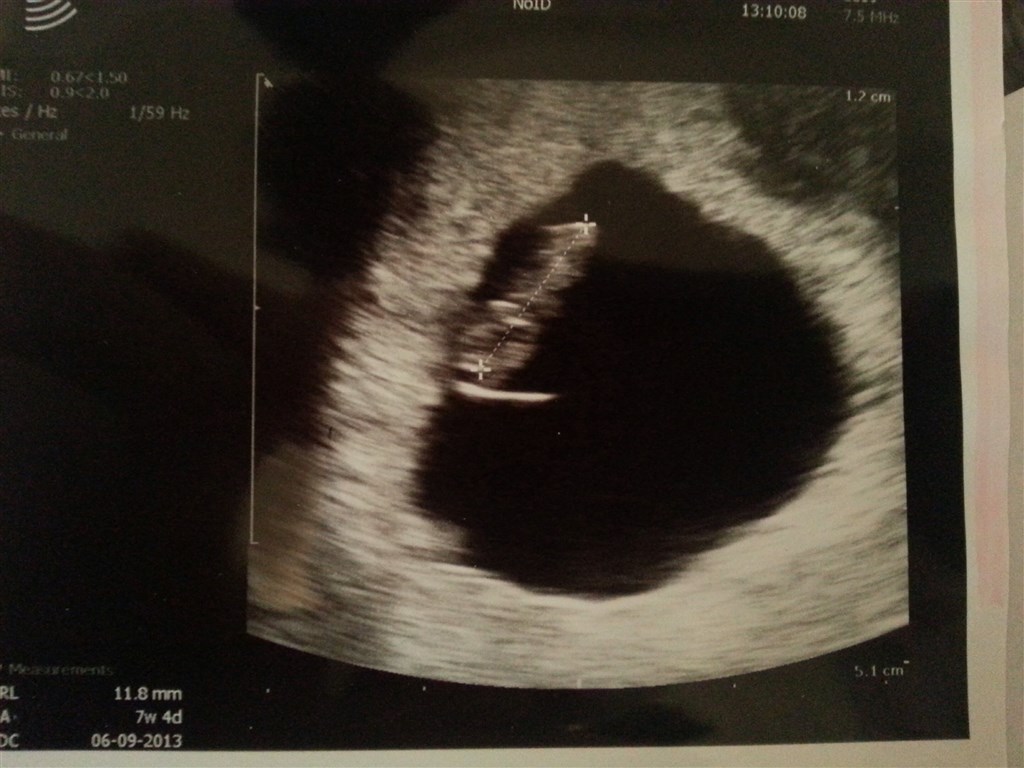

Her er mit billede fra 7+4 og der kan man tydeligt se en lille baby.

Håber at hun bare var dårlig til at scanne. Blev du scannet udvendig eller indvendig?

Vedhæftede fotos (klik for at se i fuld størrelse)